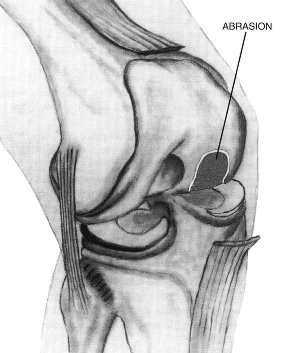

Endogenous reparation processes can be stimulated by the so-called abrasion. The abrasion is a milling of the exposed cartilage-less bone ("Moon Landscape").

Only the top dead bordering lamella is milled (about 2 mm) to expose blood vessels. The stability and carrying capacity of the joint are not reduced thereby. By exposing the blood vessels, the growth of replacement cartilage is stimulated.

Arthroscopic treatment of osteoarthritis using the example of the knee joint: The dead, exposed bone layer is removed by abrasion to stimulate the body's own recovery processes.